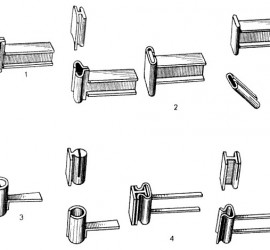

Жевательная проба. Критерий оценки эффективности работы жевательного аппарата, которую определяют по 3 показателям: жевательная эффективность, жевательный эффект и жевательная способность. Тестовым материалом для жевательной пробы могут служить пищевые продукты (орехи, морковь, хлеб) и искусственно созданные (20% желатина, отвержденная в 4% формалине, ортосил, другие пластмассы). Обязательным условием для воспроизводимости результатов пробы […]